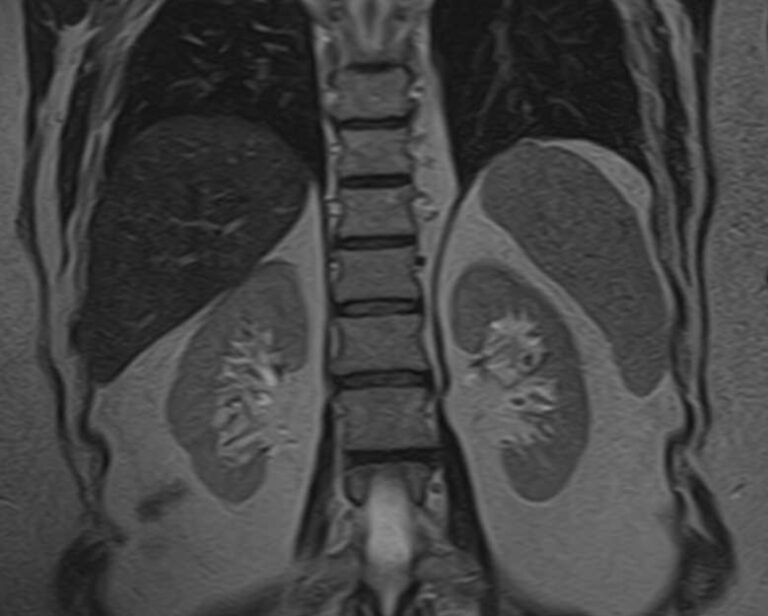

МРТ почек проводится для оценки состояния всех структур этого важнейшего органа выделительной системы, включая паренхиму, чашечки, лоханки почек и сосудистую систему. В клинике «Доступная медицина» исследование выполняется на томографе экспертного уровня TOSHIBA VANTAGE TITAN 1,5 Тесла, который обеспечивает изображения высокой четкости и контрастности, что позволяет проводить точную и достоверную диагностику заболеваний почек.

МРТ используется для диагностики злокачественных и доброкачественных опухолей почек. При этом большую ценность представляет МРТ почек с введением контрастного вещества. Процедура дает возможность не только выявить новообразования, но и установить степень развития патологического процесса, определить распространение метастазов на близлежащие органы. Только МРТ позволяет обнаружить псевдокапсулу новообразования. Такая информация крайне необходима, если речь идет об оперативном лечении рака почки с возможным сохранением органа. Также методика с высокой точностью определяет кистозные образования, распространение метастазов.

МРТ почек показывает:

- размеры мозгового и коркового слоев;

- расположение анатомических структур органа;

- функциональность;

- возможное вовлечение в патологический процесс питающих сосудов.

Исследование используется при лечении различных воспалительных и дегенеративных процессов почек с целью анализа эффективности проведенной терапии. МРТ почек назначается пациентам при наличии противопоказаний к осуществлению рентгенограммы, урографии, в случае неэффективности КТ, ультразвукового сканирования. Дополнительно во время обследования диагност может выявить заболевания мочевыводящих путей, в частности, мочеточников. Показано проведение магнитно-резонансной томографии при эндокринных патологиях (при расстройстве функций надпочечников), злокачественном течении гипертонической болезни. С помощью МРТ почек удается установить травматические повреждения, подтвердить абсцесс органа, мочекаменную болезнь, врожденные аномалии строения.